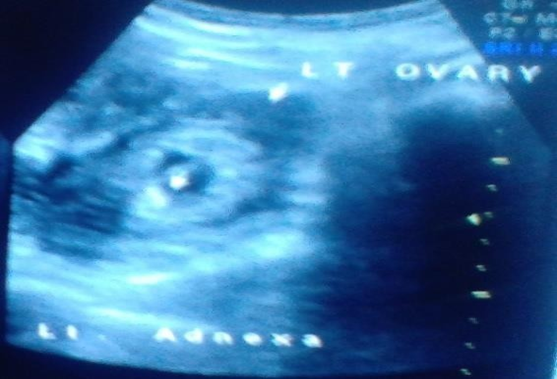

Transvaginal Sonography showed a heterogeneous mass in right adnexa with irregular Gestational sac measuring approximately 1.0 cm corresponding to 5 weeks 5 days Right ovary was visualised separately from this mass.

Left adnexa irregular Gestational sac measuring approximately 0.8cm corresponding to 5 weeks 4days. Left ovary was visualised separately from this mess .Mild to Moderate hemoperitoneum was seen .Uterus was bulky however there was no intrauterine gestational sac.

Figure 4: Trans vaginal Sonography shows both adnexae heterogeneous mass with two irregular sacs and hemoperitoneum. Both ovaries are visualised